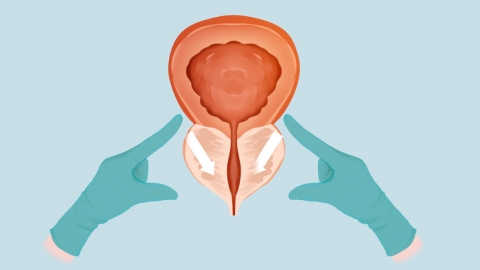

一般情况下,亚麻籽油对轻微前列腺不适且配合健康饮食时可能有辅助作用,对前列腺疾病患者仅靠其调理则难以起到帮助。如有疑虑,建议提前就医咨询。具体分析如下:

若前列腺存在轻微不适,表现为偶尔坠胀或排尿略不顺畅,日常将亚麻籽油作为健康饮食的一部分,其含有的营养成分可辅助减轻局部炎症反应,这种情况下能为前列腺健康提供一定支持。

若已确诊前列腺炎、前列腺增生等疾病,出现明显疼痛、排尿困难等症状,仅依靠亚麻籽油无法治疗病症,其作用远不及规范医疗干预,此时难以对前列腺健康起到实质帮助,还可能延误治疗时机。

食用亚麻籽油需控制用量,避免高温烹饪破坏营养。若前列腺不适持续或加重,应及时就医检查,遵循专业指导进行治疗,勿依赖单一食材调理而忽视科学干预。